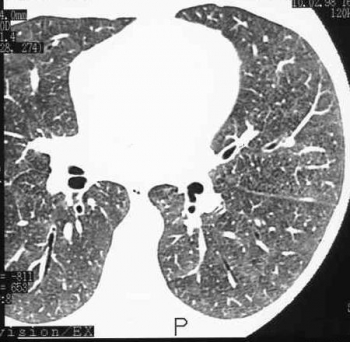

Silikoz teşhisi nasıl yapılır ?

Söz konusu hastanın geçmiş hal durumu incelenir, çalıştığı yerdeki toz numuneleri gözden geçirilir ve röntgen filmlerinde ciğerde görünen karaktetistik görüntüler dikkate alınır.